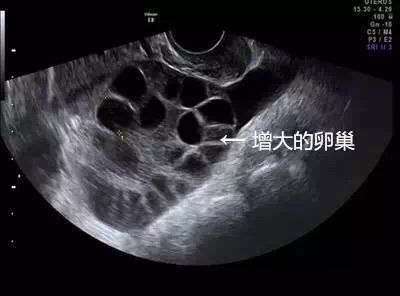

22岁琳琳看了中介广告去卖卵,取卵后第5天出现持续性下腹胀、十分明显的胸闷,随后在妇幼院做B超提示腹腔内大量积液,胸腔少量积液,卵巢增大超过3倍以上。术后多次复查,她的卵巢也未恢复到正常情况。

卵巢囊性增大、腹腔积液、胸腔积液、水肿、血液高凝形成血栓、肾衰竭......这就是医学上所说的卵巢过度刺激综合征(OHSS),严重时可危及生命。